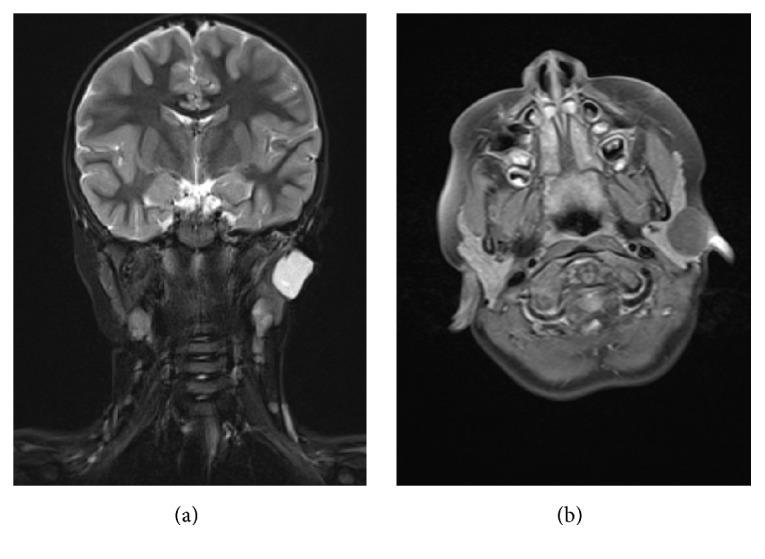

报告中最年轻且成功接受治疗的腮腺皮样囊肿患者:一例罕见的儿科病例。

The Youngest Reported and Successfully Treated Patient with a Dermoid Cyst of the Parotid Gland: A Rare Pediatric Case.

Dermoid cysts (DCs) are rare benign, epithelial-lined lesions. Up to 7% of them are found in the head and neck region and 80% of those predominantly occur in the orbit, in the nose, and in the floor of the mouth. The average age of presentation is around the age of six. Dermoid cysts located in the parotid gland have only been published in 19 cases so far. Interestingly, the mean age of occurrence in the parotid gland was much higher (31 years). We report on a four-year-old girl being the youngest patient who had ever been diagnosed with this disease.

皮样囊肿(DCs)是罕见的良性上皮内衬性病变。其中高达7%位于头颈部区域,而这些病变中的80%主要发生在眼眶、鼻腔和口底。发病的平均年龄约为6岁。位于腮腺的皮样囊肿迄今为止仅有19例发表。有趣的是,发生在腮腺的平均年龄要高得多(31岁)。我们报告了一名4岁女孩,她是有史以来被诊断患有这种疾病的最年轻患者。